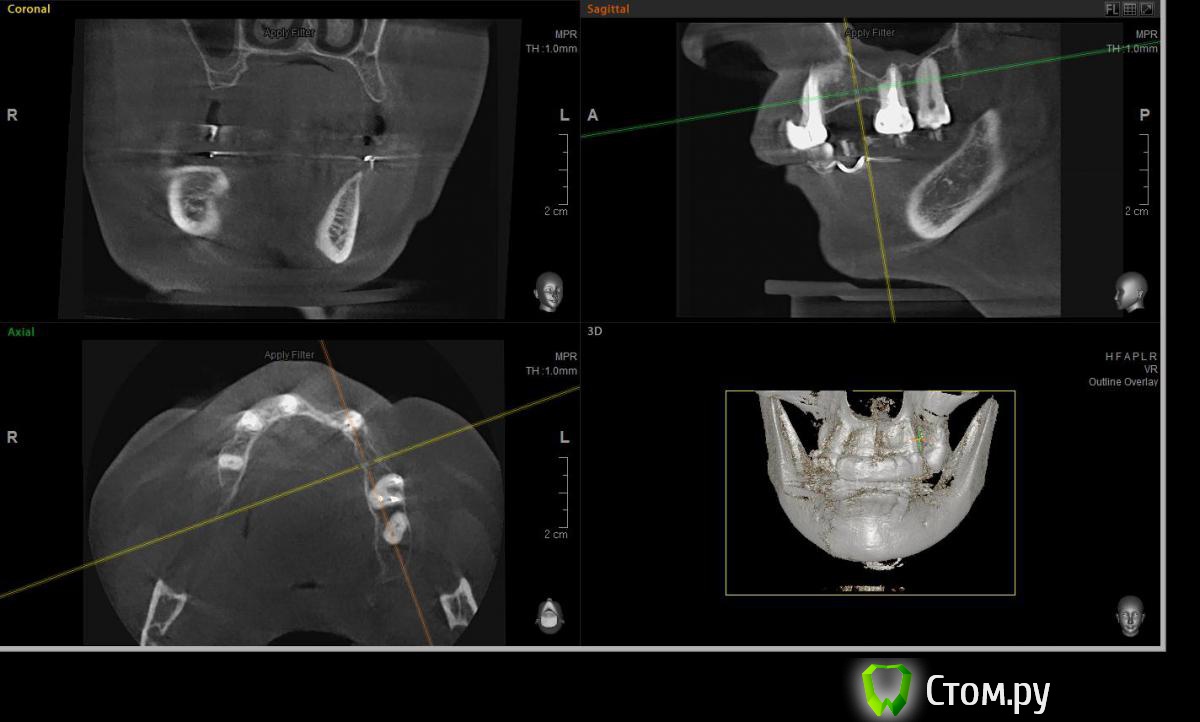

Евгений Ходыкин Опубликовано 22 июля, 2014 Автор Поделиться Опубликовано 22 июля, 2014 Дабы не плодить тем решил очередной случай выложить сюда Решили с пациенткой пока начать с в.ч. В планах имплантация в область отсутствующих 1.6, 1.4, 1.2, 2.1, 2.2, 2.4, 2.5. С 1.6 самому более менее все понятно, мануальных навыков хватит) Прошу помощи коллег относительно остальных областей. Фронт особливо печален... Забегая наперед скажу, что блоки еще не делал. Ауто точно пока брать не планирую, ибо нет даже теоретических навыков. Хочу начать все-таки с аллоблоков. У кого какие будут мнения, заранее спасибо) Ссылка на комментарий